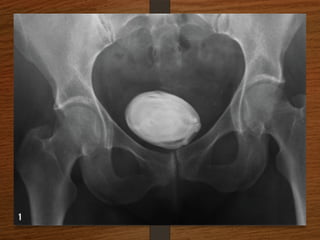

What are the D/D of a radiopaque shadow in this region?

• Kidney stone

• Gallstones

• Pancreatic calculi

• Foreign body

• Fecolith

• Phleboliths

• calcified lymph node

• calcified renal tuberculosis

• calcified adrenal gland

• chip fracture of a transverse process of vertebra or calcification of costal

cartilage